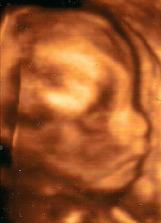

Pro Lukáška

Tak už víme, že náš drobeček bude kluk ... mamince se splnilo velké přání : ))) tatínek chtěl raději holčičku, teď už ale s radostí nakupuje "chlapské" věci a holčičku si prý "uděláme" dodatečně